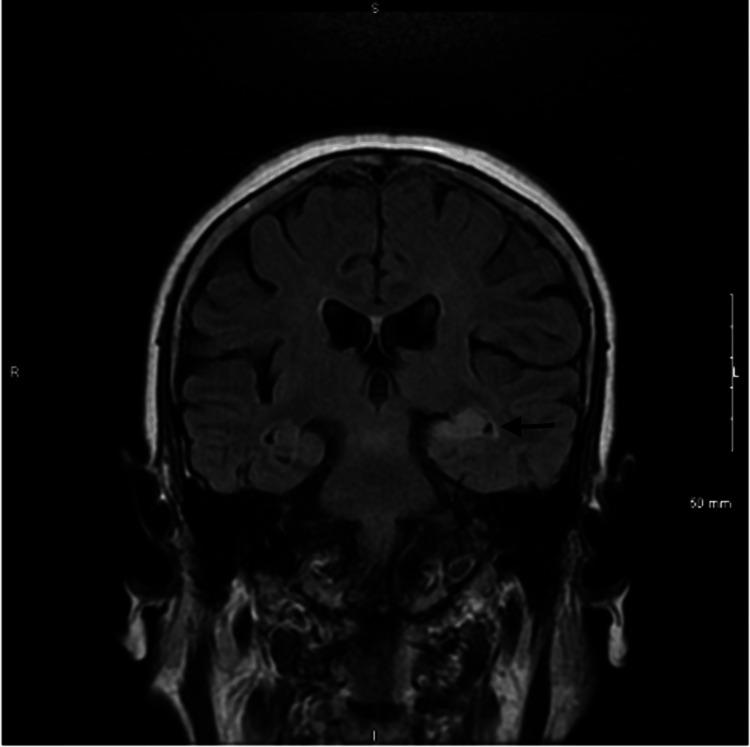

Whole-brain metabolic pattern analysis in patients with anti-leucine-rich glioma-inactivated 1 (LGI1) encephalitis.

Eur J Neurol. 2022 Aug;29(8):2376-2385. doi: 10.1111/ene.15384. Epub 2022 May 29.